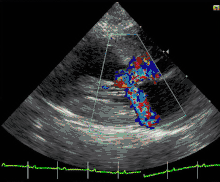

.jpg)

A diagnosis of hypertrophic cardiomyopathy is based upon a number of features of the disease process. While there is use of echocardiography, cardiac catheterization, or cardiac MRI in the diagnosis of the disease, other important considerations include ECG, genetic testing (although not primarily used for diagnosis),[31] and any family history of HCM or unexplained sudden death in otherwise healthy individuals.

In about 60 to 70% of the cases, cardiac MRI shows thickening of more than 15 mm of the lower part of the ventricular septum. T1-weighted imaging may identify scarring of cardiac tissues while T2-weighted imaging may identify oedema and inflammation of cardiac tissue which is associated with acute clinical signs of chest pain and fainting episodes.[32]